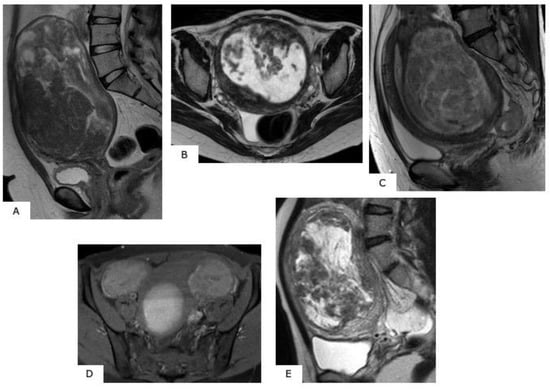

LMS accounts for approximately one-third of all uterine sarcomas. The majority of LMS are observed in perimenopausal women aged 50–55 years, although 15% are noted in women aged less than 40 years. The following are well-known MRI findings for a suspected LMS: (1) high signals in T2WI and abnormal signals in DWI, (2) high signals in T1WI, and (3) ill-defined tumor mass borders (Figure 3) [3], with (1) showing high cell density in the mass and (2) suggesting hemorrhage within the mass and (3) an infiltrative growth of mass, a finding strongly suggestive of malignant tumor. In some cases, an image may show an exposure of the mass to extrauterine serosa, while in other cases, the mass has infiltrated to the surrounding normal myometrium and endometrium. This latter radiological interpretation should evoke special precaution. In contrast-enhanced images, a mass that shows an early period of heterogeneous, strong contrast effect is considered to be a tumor mass. However, the hemorrhagic necrosis portion of a mass—essential for the diagnosis of LMS—is considered to be an area where contrast effects are missing [4] (Figure 4 and Figure 5).

Figure 4.

Magnetic resonance images of leiomyosarcoma. (A,B): T1-weighted sagittal sections, (C,D): T2-weighted sagittal sections. In the myometrium, in T2-weighted images, overall, there is high signal intensity with ill-defined borders; in T1-weighted images, there is mass accompanied by internal hemorrhage. Follow-up observation was selected for this case, with the diagnosis of uterine sarcoma 1 year thereafter.

Figure 5.

Magnetic resonance images of leiomyosarcoma (age, 49 years). (A,B): T2-weighted images sagittal sections, (C): T1-weighted axial section, (D): contrast T1 fat-suppression axial section. In the myometrium, heterogeneous high signals are presented with T2-weighted images, and with T1-weighted images, there is confirmation of mass showing faint high signals considered to be hemorrhage. In the contrast T1 fat-suppression image (D), a poorly contrasted area considered to be necrosis is found, while in (B), the fundus uteri side shows extremely thin myometrium, together with finding a portion considered to be extraserosal exposure, with ill-defined tumor borders (arrow).